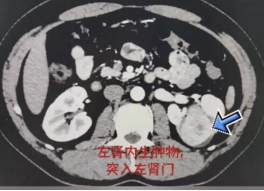

虽是隔着屏幕的陌生人,但中肿专家专业的态度和耐心的解答就给了患者极大的信心。入院后经过一系列检查,增强CT结果显示:左肾病灶,考虑肾癌可能性大,完全内生,瘤体最大径5.6cm。这复杂的情况,对保肾确实很有难度。

因为患者年轻且保肾意愿强烈,董培副主任医师仔细询问病史,患者无血尿,考虑集合系统仅是压迫,并没累及,肿物边界清楚,并提出了该肿瘤是从外面向里生长,因此可以切除病灶并保肾。这对患者和家庭来说真的是惊天的喜讯,对治疗看到了希望。